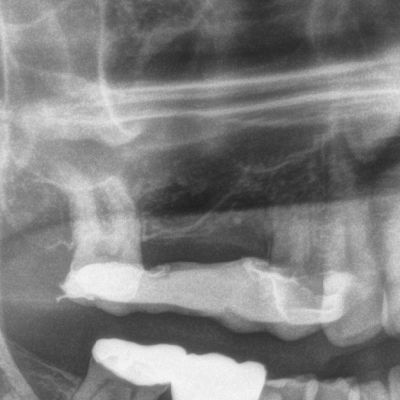

Sinuslift mit Eigenknochen und späterer Implantation

Fehlende Zähne 15,16